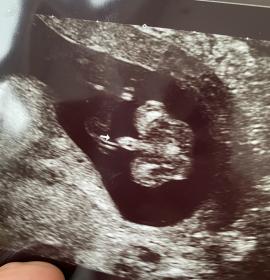

Tricky NUB 13+1 weeks? Long NUB but some stacking?

I had a scan yesterday (13+1 weeks!). During the scan I was convinced I saw long somewhat flat, but also a stacked nub (I saw a shadow in the background), but the tech said it was the stacking was the umbilical cord. The tech said she saw a flat NUB that I is why she was leaning more towards girl.

I posted my scans online and got mostly boy guesses (some girl because of the "flat" NUB) but I was wondering if it's still possible it might be a girl? That the "stacked thing" is something else??? (Already got 3 boys so a girl would be so welcome!)